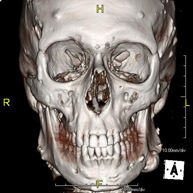

- Facial mass CT

Radiological test that provides high definition anatomical images of the facial mass (face) using CT (Computed Tomography) equipment. Indicated for: tumours, plastic surgery.

- Dental CT

Radiological test that provides high definition anatomical images of the maxillary bone (teeth, dental nerve path) using CT (Computed Tomography) equipment. Indicated for: examination prior to dental extraction, examination prior to implants, tumours, abscess.